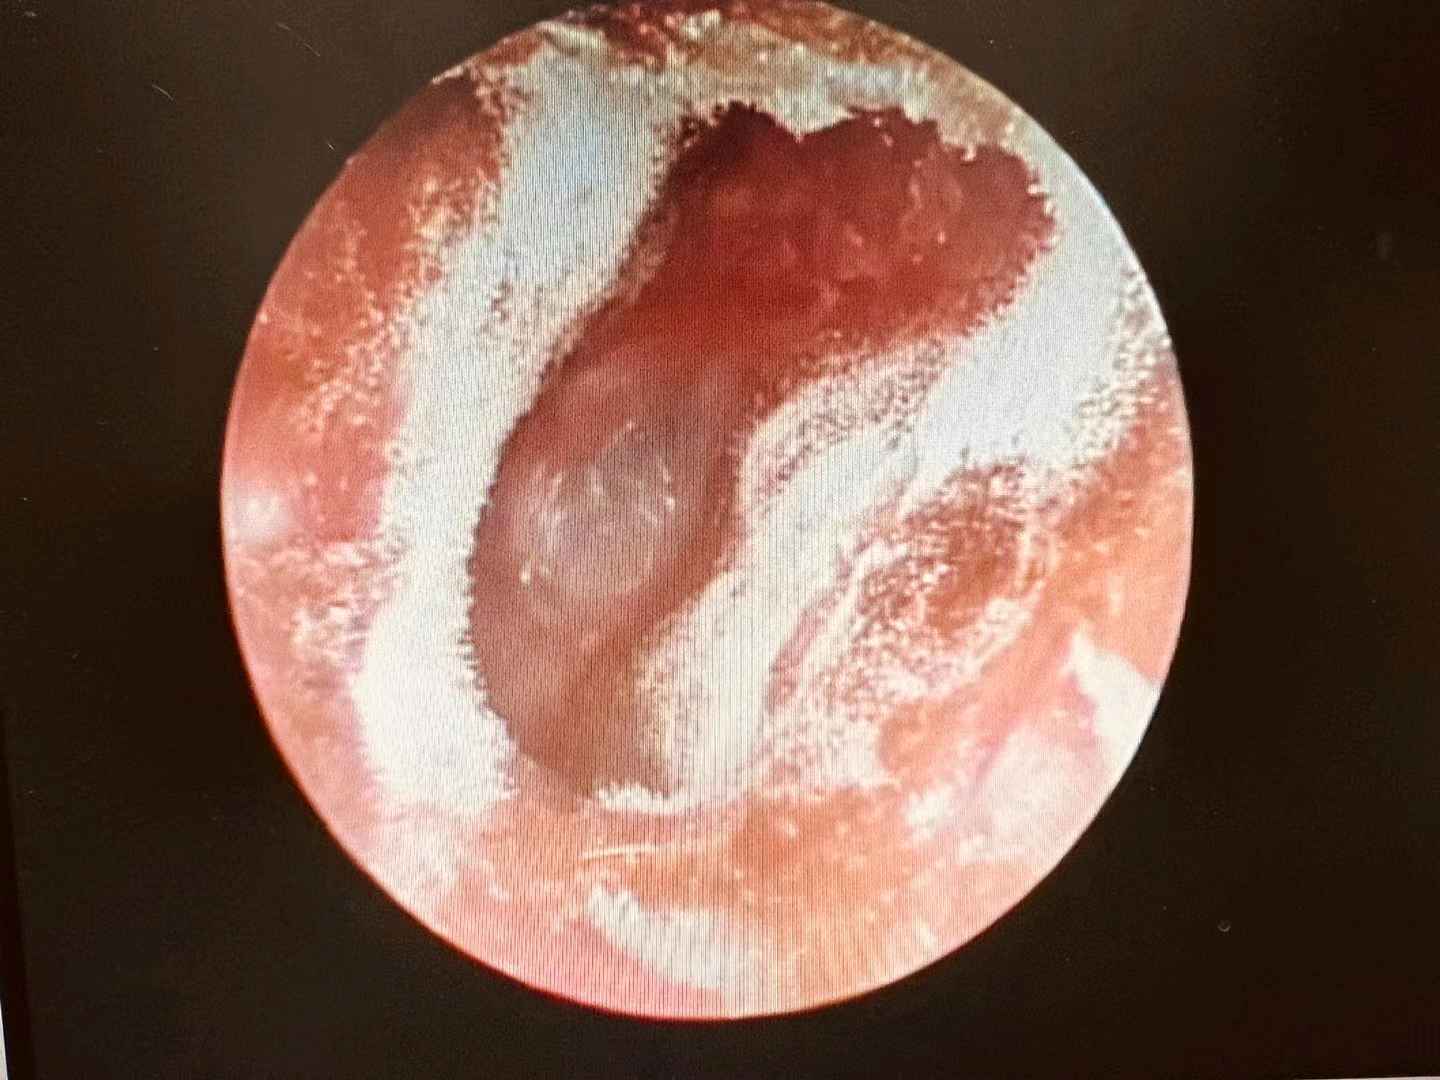

才知道得了急性中耳炎

儿童急性中耳炎是指细菌和(或)病毒等病原体经咽鼓管直接进入鼓室引起中耳腔黏膜感染。急性中耳炎最常见的致病菌主要为肺炎链球菌(约占70%),其次为未分型流感嗜血杆菌(约占20%)、卡他莫拉菌、金黄色葡萄球菌等。

如果治疗不及时,发炎部位会化脓,化脓后仍然得不到有效治疗,耳鼓膜就会出现穿孔,耳孔流出脓水,流脓可持续三四天到一两周。